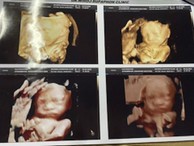

ได้ลูกสาวคนที่ 2 ค่ะ

Post reply image